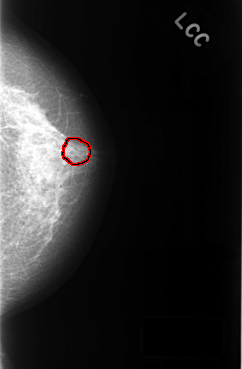

C_0320_1.LEFT_CC

LEFT_CC LINES 4424 PIXELS_PER_LINE 2904 BITS_PER_PIXEL 12 RESOLUTION 50 OVERLAY

FILE: C_0320_1.LEFT_CC.OVERLAY

TOTAL_ABNORMALITIES 1

ABNORMALITY 1

LESION_TYPE CALCIFICATION TYPE PUNCTATE DISTRIBUTION CLUSTERED

ASSESSMENT 4

SUBTLETY 3

PATHOLOGY BENIGN

TOTAL_OUTLINES 1

BOUNDARY